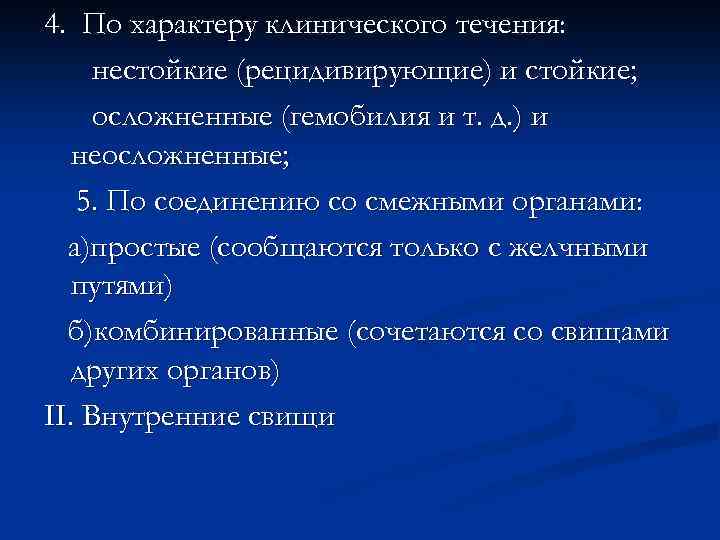

4. По характеру клинического течения: нестойкие (рецидивирующие) и стойкие; осложненные (гемобилия и т. д. ) и неосложненные; 5. По соединению со смежными органами: а)простые (сообщаются только с желчными путями) б)комбинированные (сочетаются со свищами других органов) II. Внутренние свищи

4. По характеру клинического течения: нестойкие (рецидивирующие) и стойкие; осложненные (гемобилия и т. д. ) и неосложненные; 5. По соединению со смежными органами: а)простые (сообщаются только с желчными путями) б)комбинированные (сочетаются со свищами других органов) II. Внутренние свищи